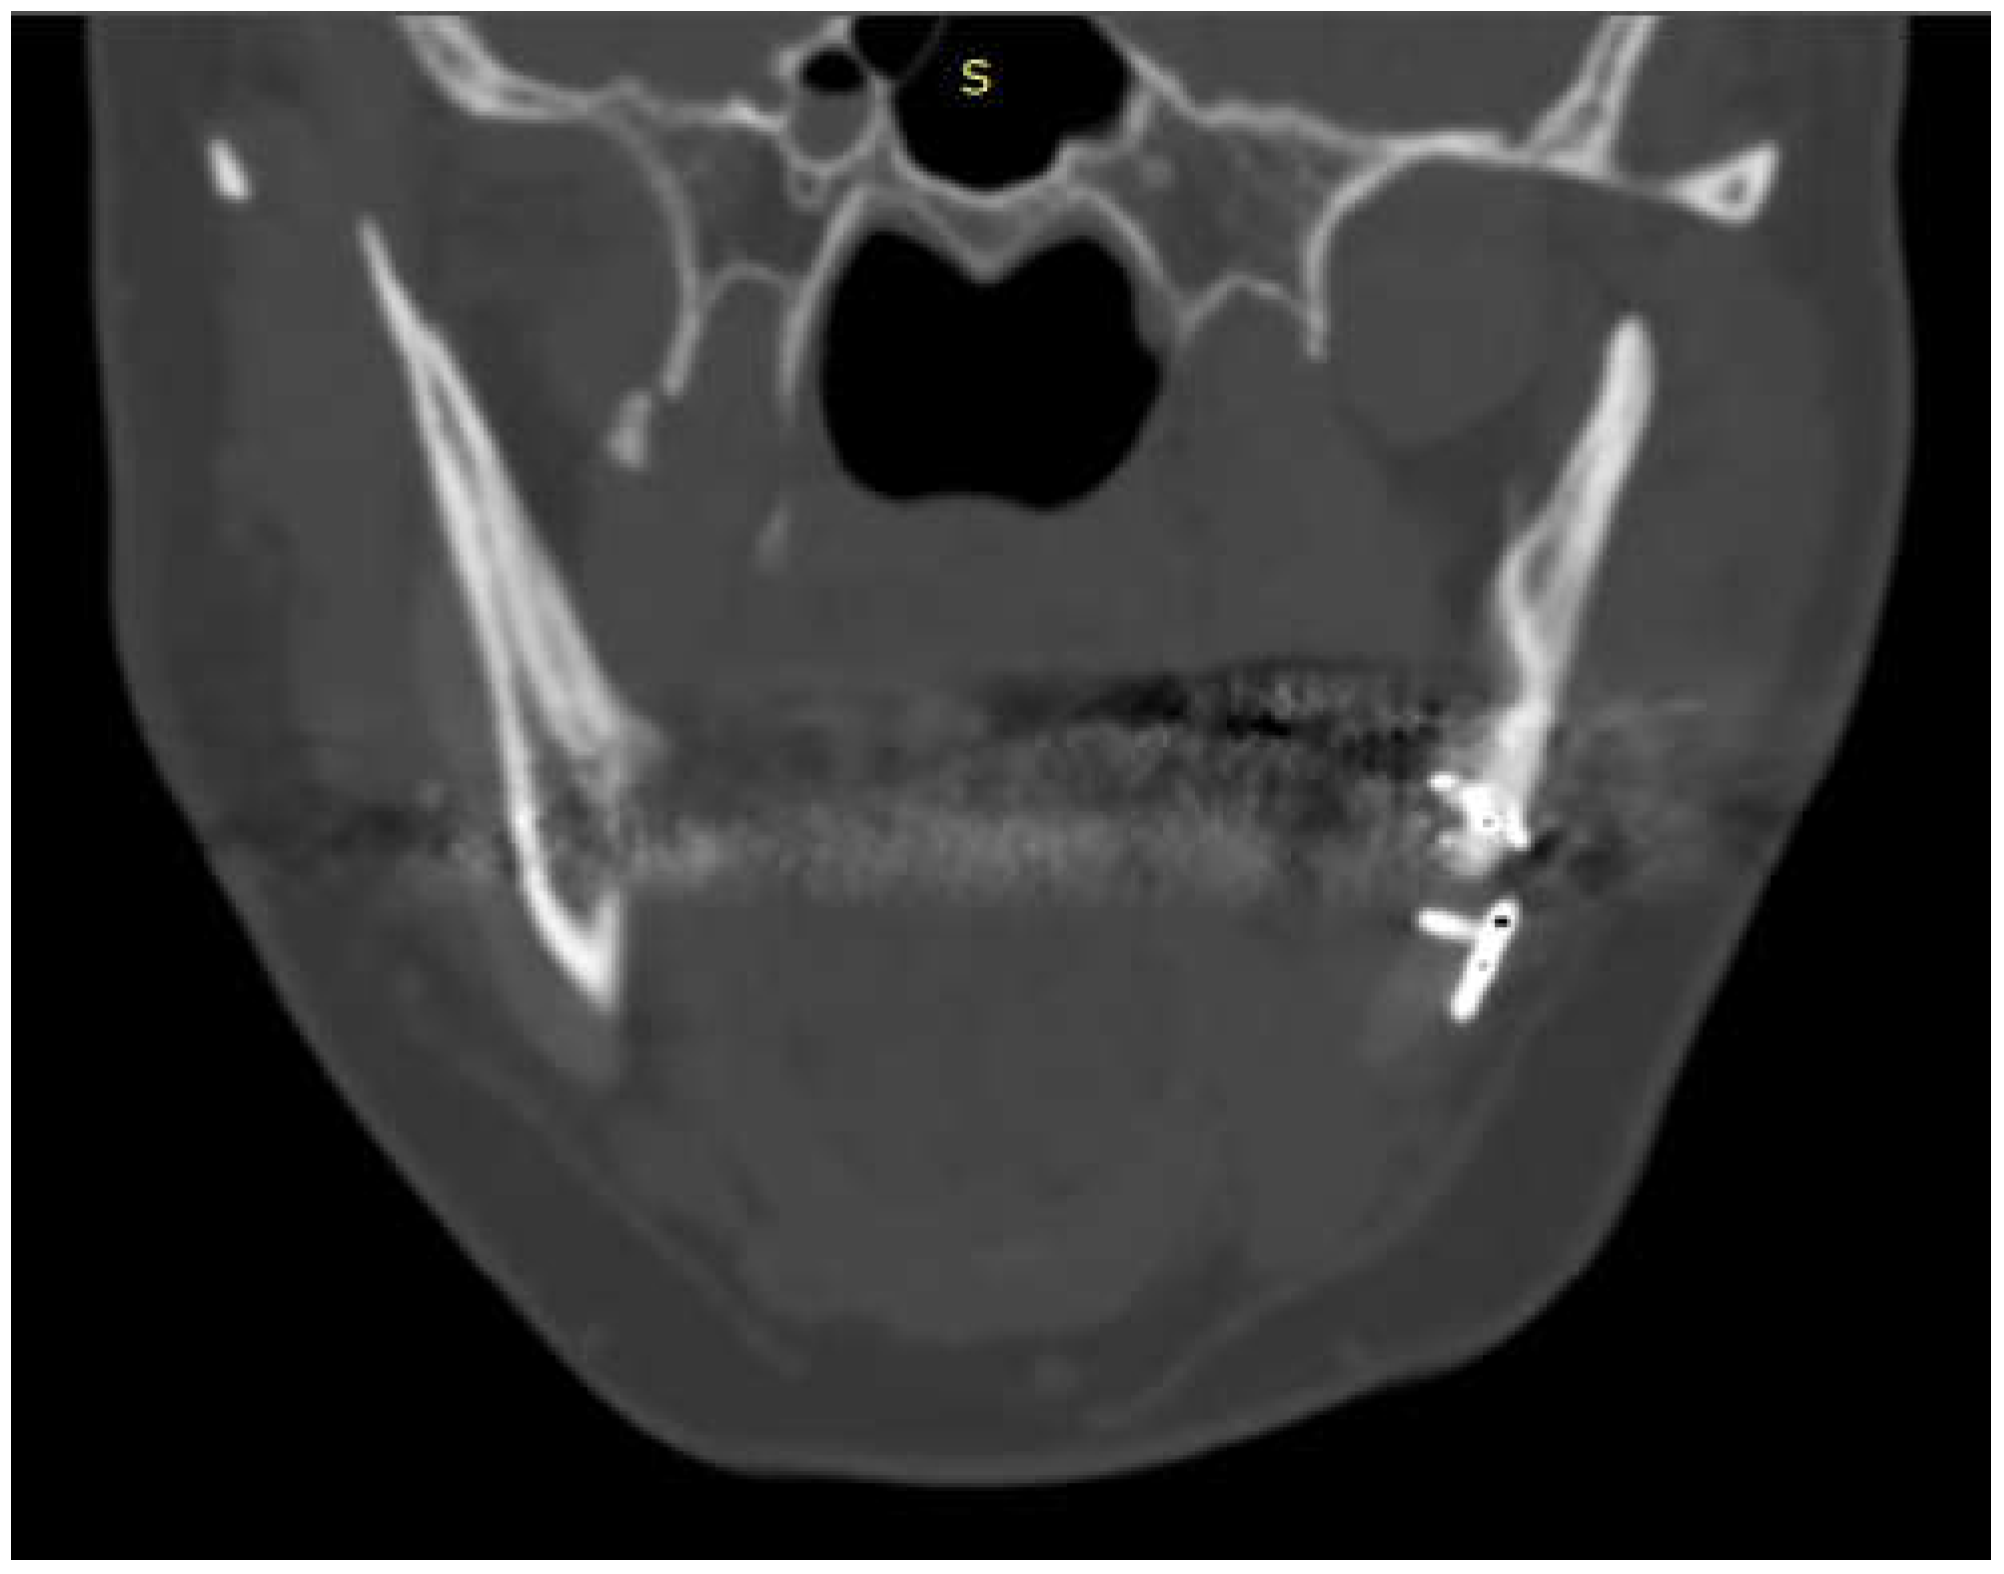

Postoperative CT scan of 11 patients were studied. In 11 out of 12 CT scan was possible to note radiological evidence of bone regrowth on the surface and edges of the implant; in those implants where factory created holes were present, bone regrowth was also noted in them.

The case of maxillofacial surgery where bone regrowth was not observable underscores the importance of a sufficient bone prosthesis interface for a successful osteointegration (see Figure 3). The neurosurgical case series, in which the interface between bone and prosthesis for cranioplasty is minimal, further corroborated this statement. Studies have shown that a larger contact area between the implant and bone facilitates osteoblastic activity and bone ingrowth [44]. In addition, that implants with roughened surfaces or porous coatings promote greater bone ingrowth compared to smooth-surfaced implants [45,46]. For this reason, factory-created holes are a valuable aid in the creation of bone tissue within them, as demonstrated in the previously analyzed case. Other studies aimed at enhancing the bioactivity of PEEK to improve the bone-implant interface are still in the in vitro stage, but we anticipate significant progress soon [47,48].

Figure 1. Bone formation in factory created holes of PEEK prosthesis.